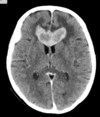

35 anos

Hemangioblastoma